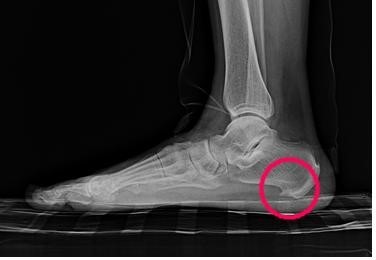

초기에는 밤에만 불편함을 느끼다가 점점 지속 시간도 늘어납니다.3. 족저근막염

발바닥 통증의 대표 질환으로,

발뒤꿈치에서 발바닥 전체로 이어지는 근막에 염증이 생기며

걷거나 서 있을 때 발바닥이 뜨겁고 찌릿한 통증을 유발합니다.

특히 아침에 첫 발을 디딜 때 더 아픈 경우가 많아요.